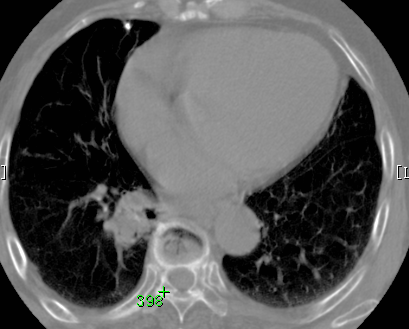

标题: CT26680:肺部右下肺静脉干结节的界定 [打印本页]

标题: CT26680:肺部右下肺静脉干结节的界定

经追查说有支扩咯血病史,但不确定

考虑1、周围型肺癌,2肺静脉畸形,前者可能大,建议增强检查。

考虑1、周围型肺癌,2肺静脉畸形,前者可能大,建议增强检查。支持!

不排除右肺下叶周围型肺癌可能。

中心型肺癌,纤支镜可帮助明确。